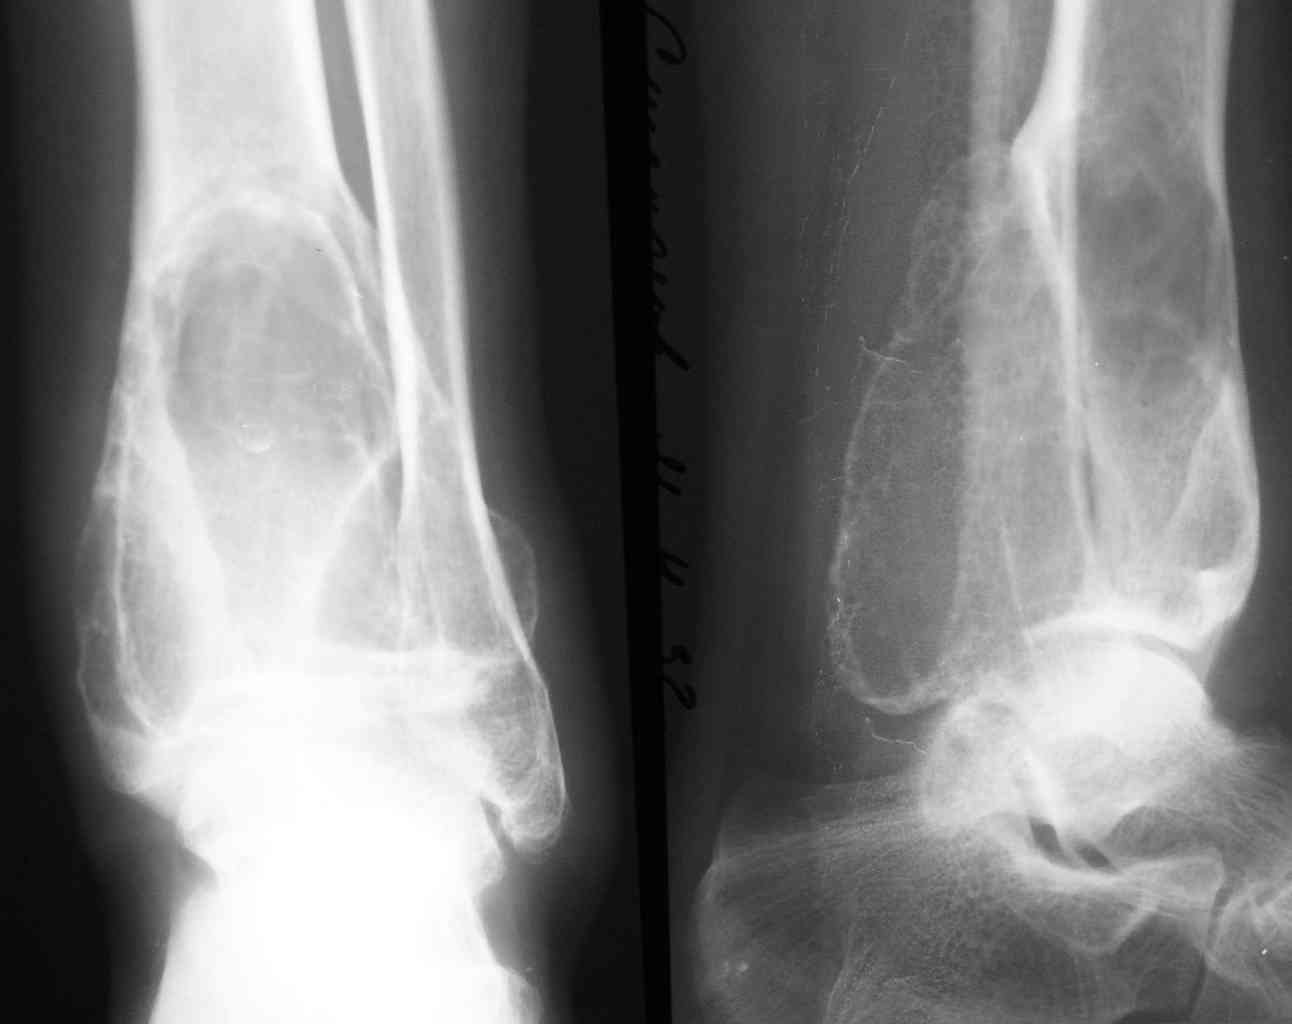

1-Пациент Х.18лет, аневризмальная костная киста малоберцовой кости и основной фаланги I пальца левой стопы (Рис. 1,2).

2-Пациент С.,32 лет,аневризмальная костная киста левой большеберцовой кости (Рис. 3,4), проходит лечение.